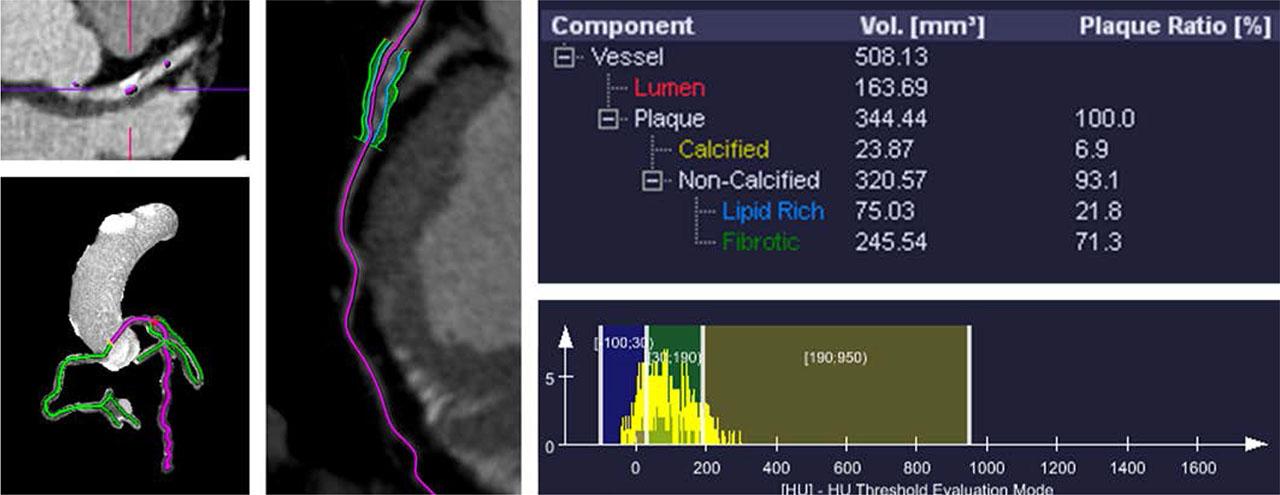

For further evaluation of the plaque characteristics and components of this severe lesion, we utilized our offline workstation, syngo.via Frontier® (Syngo.Via, Siemens Healthineers). This advanced system allowed us to precisely measure various types of plaque volumes. These included the total plaque volume (TPV), calcified plaque volume (CPV), non-calcified plaque volume (NCPV), lipid-rich plaque volume (LRPV), and fibrotic plaque volume (FPV). The analysis highlighted the presence of a mixed plaque in our case. Specifically, the TPV was measured at 344.44 mm3, with a CPV of 23.87 mm3 and an NCPV of 320.57 mm3. Further breakdown of the NCPV revealed an LRPV of 75.03 mm3 and an FPV of 245.54 mm3. All these results are depicted in Figure 5.

Syngo.via Frontier® analysis of the mixed plaque at the proximal LAD